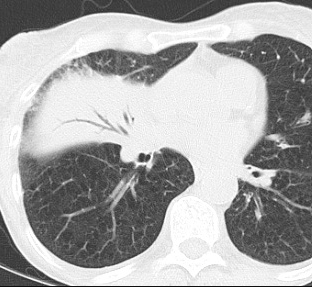

환자가 누운 자세, 즉 supine 상태일 경우에는

폐의 posterior segment나 superior segment of lower lobe에 병변이 생기는 경우가 많다.

반면 환자가 앉거나 서 있는 상태에서는

lower lobe basal segment가 더 흔하게 침범된다.

그러나 중환자는 대부분 누운 자세이기 때문에

실제 임상에서는 폐의 posterior lower lung에서 aspiration pneumonia가 나타나는 경우가 많다.

영상에서 aspiration pneumonia를 atelectasis와 구분하는 것은 매우 중요하다.

두 질환 모두 폐의 posterior lower lung에 음영 증가가 나타날 수 있기 때문이다.

그러나 atelectasis에서는

폐 용적 감소(volume loss)가 나타나는 경우가 많고

fissure 이동이나 종격동 이동 같은 소견이 동반될 수 있다.

반면 aspiration pneumonia에서는

폐 용적 감소가 뚜렷하지 않고

폐 실질 내부에 patchy consolidation이 나타나는 경우가 많다.